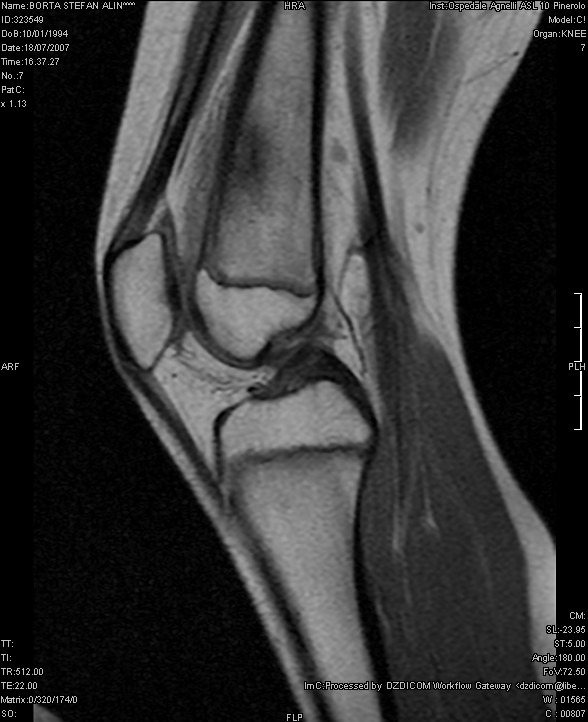

S. veniva dunque ricoverato presso il nostro Reparto di Pediatria. Gli esami di laboratorio inizialmente eseguiti erano normali e la radiografia del ginocchio non evidenziava anomalie. Veniva eseguita una TAC dell'arto inferiore dx che evidenziava una lesione di circa 5 mm di diametro a livello della corticale del femore distale, compatibile con OO (Figura 1). In seguito la scintigrafia total-body con Tecnezio-99 dimostrava una intensa captazione del tracciante a livello della diafisi distale del femore destro, con segni di ipervascolarizzazione e di aumentata attivit� osteoblastica. Per meglio definire la lesione veniva eseguita anche una Risonanza magnetica Nucleare (RMN) che confermava la presenza di un quadro compatibile con OO (Figura 2).

La lesione alla TAC � piuttosto caratteristica: l'aspetto tipico di un'immagine lacunare osteolitica di piccole dimensioni circondata da una reazione sclerotica iperdensa � quasi sempre dirimente. Per la diagnosi differenziale (soprattutto con tumori ossei e istiocitosi) � utile l'esecuzione della scintigrafia ossea con Tecnezio-99 e della RMN, che pu� evidenziare la diffusione ai tessuti molli e l'eventuale coinvolgimento intramidollare (in caso di lesioni a localizzazione vertebrale).

Figura 2. La RMN del femore dx conferma la presenza della lesione evidenziata alla TC.